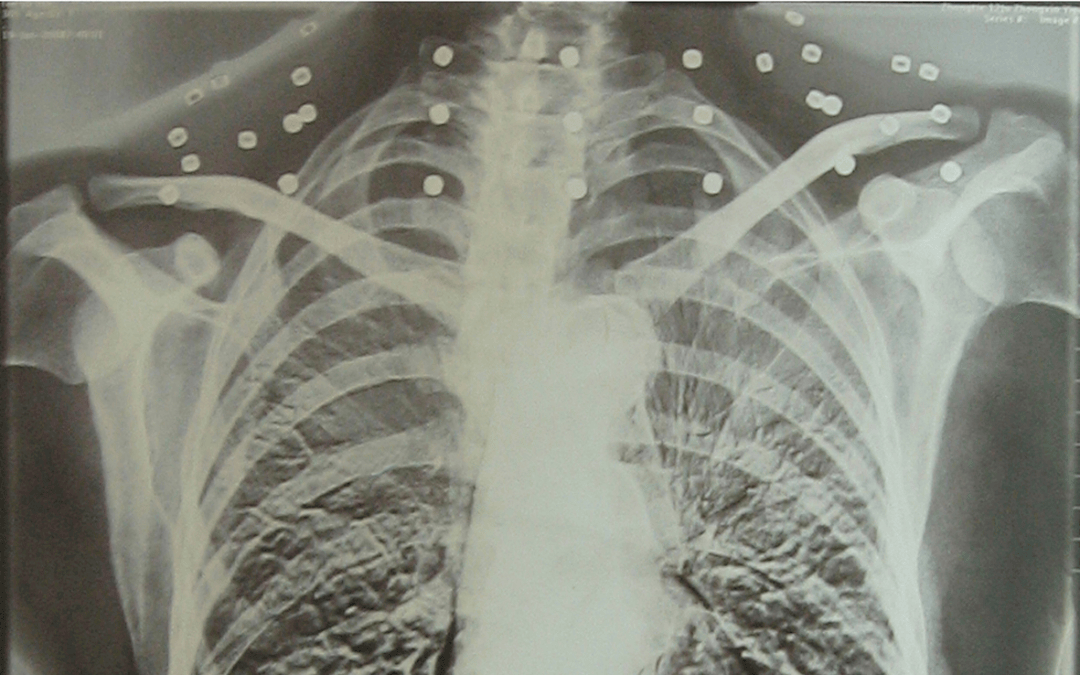

这张照片

是今年82岁的吴以先老人

拍摄的一张CT照

但实际上是

吴以先的颈部和腹部

共分布着33枚弹片

他体内的弹片都没有取出

身体留有弹片的位置就有痛感

但吴以先不考虑取出弹片

在他看来

这是他与战友并肩作战的见证

是他的勋章

岁月虽逝,硝烟散去

但那份军人的荣耀与担当

与吴以先身上那33枚弹片

一起永远烙印在他心中

33枚“军功章”

是一名军人的光荣

也是一位英雄的至诚本色